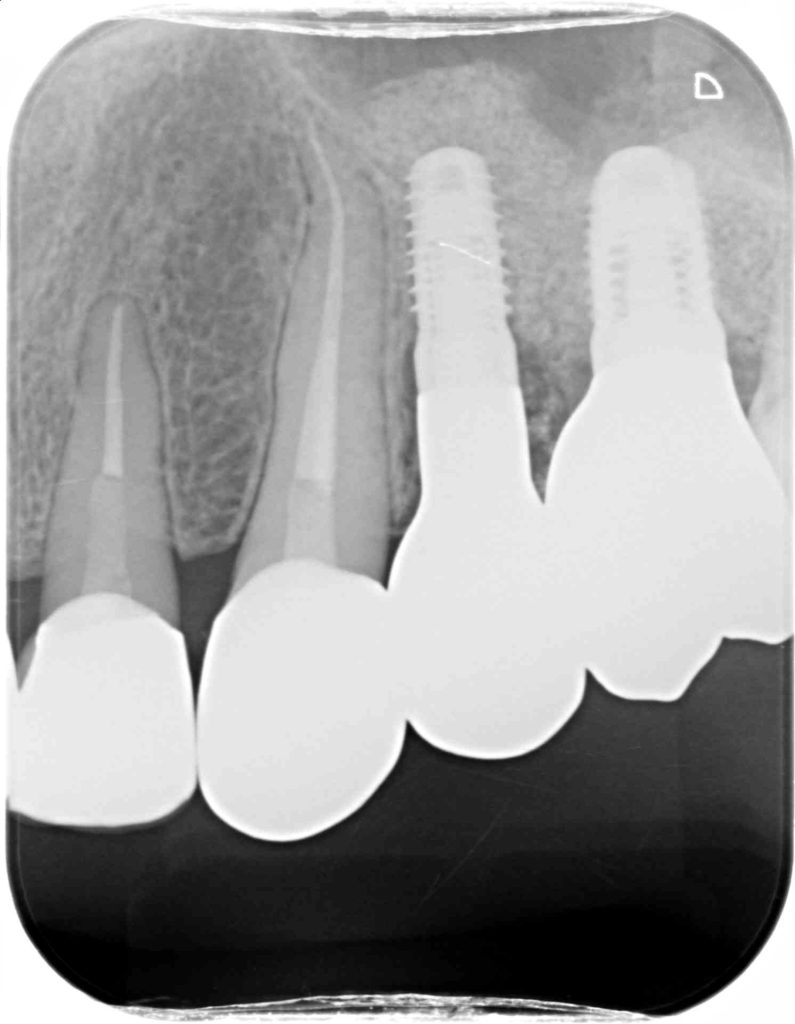

下記の症例は当院の審美領域のインプラント治療の治療結果となります。

治療後、どの歯を抜歯してインプラント治療を行ったか見分けがつかないような治療結果に拘っています。

治療後のクオリティーはもちろん、できるだけ負担の少ない術式を意識し、患者ファーストを第一に考えております。

この症例に発生する費用 約85万円(税抜)